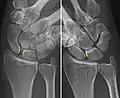

Dynamic instability: Increased scapholunate distance (between yellow lines) upon ulnar deviation of the wrist, but not otherwise.

X-ray images indicate scapholunate ligament instability when the scapholunate distance is more than 3 mm, which is called scapholunate dissociation.[7] A static scapholunate instability is generally readily visible, but a dynamic scapholunate instability can only be seen radiographically in certain wrist positions or under certain loading conditions, such as when clenching the wrist, or loading the wrist in ulnar deviation.[6]